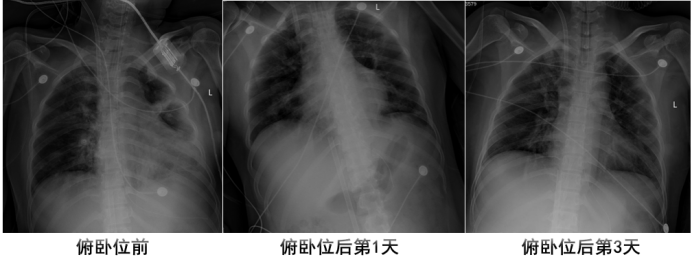

924下午开始进行俯卧位通气12 h。复查床旁胸片可见:9月24日(俯卧位前)右肺似乎略好,但左肺实变及下肺透亮度依然很差,没有完全膨胀。9月25日(俯卧位后第1天)双肺透亮度较前明显好转。9月27日(俯卧位后第3天)患者肺部病变持续好转(图9)。通过监测发现,俯卧位后,患者的静态肺顺应性明显好转(24→61 L/cmH2O)。

图片

9  俯卧位前后患者胸片变化情况